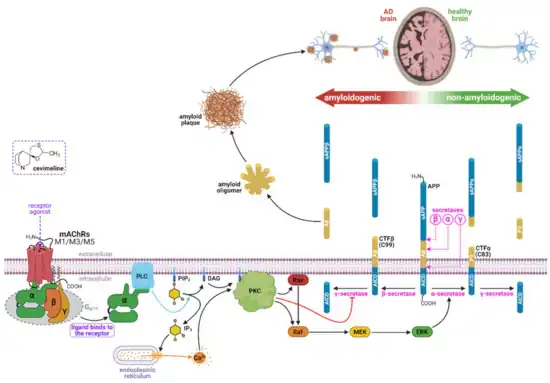

Cholinergic hypothesis

The oldest hypothesis, on which most currently available drug therapies are based, is the cholinergic hypothesis,[52] which proposes that AD is caused by reduced synthesis of the neurotransmitter acetylcholine. The cholinergic hypothesis has not maintained widespread support, largely because medications intended to treat acetylcholine deficiency have shown unsatisfactory results.[53]

Amyloid hypothesis

In 1991, the amyloid hypothesis postulated that extracellular amyloid beta (Aβ) deposits are the fundamental cause of the disease.[54][55] Support for this postulate comes from the location of the gene for the amyloid precursor protein (APP) on chromosome 21, together with the fact that people with trisomy 21 (Down Syndrome) who have an extra gene copy almost universally exhibit at least the earliest symptoms of AD by 40 years of age.[56][57] Also, a specific isoform of apolipoprotein, APOE4, is a major genetic risk factor for AD. While apolipoproteins enhance the breakdown of beta amyloid, some isoforms are not effective at this task (such as APOE4), leading to excess amyloid buildup in the brain.[58] Further evidence comes from the finding that transgenic mice that express a mutant form of the human APP gene develop fibrillar amyloid plaques and Alzheimer's-like brain pathology with spatial learning deficits.[59]

An experimental vaccine was found to clear the amyloid plaques in early human trials, but it did not have any significant effect on dementia.[60] Researchers have been led to suspect non-plaque Aβ oligomers (aggregates of many monomers) as the primary pathogenic form of Aβ. These toxic oligomers, also referred to as amyloid-derived diffusible ligands (ADDLs), bind to a surface receptor on neurons and change the structure of the synapse, thereby disrupting neuronal communication.[61] One receptor for Aβ oligomers may be the prion protein, the same protein that has been linked to mad cow disease and the related human condition, Creutzfeldt–Jakob disease, thus potentially linking the underlying mechanism of these neurodegenerative disorders with that of Alzheimer's disease.[62]

Biochemistry

Alzheimer's disease has been identified as a protein misfolding disease (proteopathy), caused by plaque accumulation of abnormally folded amyloid beta protein and tau protein in the brain.[100] Plaques are made up of small peptides, 39–43 amino acids in length, called amyloid beta (Aβ). Aβ is a fragment from the larger amyloid precursor protein (APP). APP is a transmembrane protein that penetrates through the neuron's membrane. APP is critical to neuron growth, survival, and post-injury repair.[101][102] In Alzheimer's disease, gamma secretase and beta secretase act together in a proteolytic process which causes APP to be divided into smaller fragments.[103] One of these fragments gives rise to fibrils of amyloid beta, which then form clumps that deposit outside neurons in dense formations known as senile plaques.[97][104]

Disease mechanism

Exactly how disturbances of production and aggregation of the beta-amyloid peptide give rise to the pathology of AD is not known.[107][108] The amyloid hypothesis traditionally points to the accumulation of beta-amyloid peptides as the central event triggering neuron degeneration. Accumulation of aggregated amyloid fibrils, which are believed to be the toxic form of the protein responsible for disrupting the cell's calcium ion homeostasis,[109] induces programmed cell death (apoptosis).[110] It is also known that Aβ selectively builds up in the mitochondria in the cells of Alzheimer's-affected brains, and it also inhibits certain enzyme functions and the utilisation of glucose by neurons.[111]